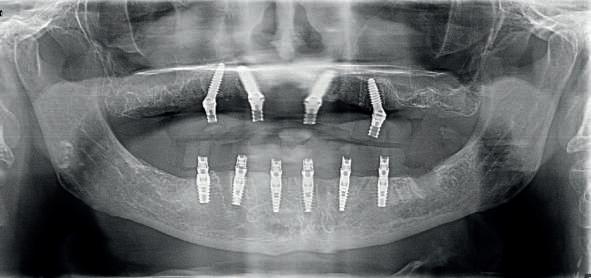

Upon physical examination we found absence of teeth in both jaws and remaining teeth with recurrent caries, advanced periodontal disease and mobility; with a poor prognosis for function and aesthetics. We proceeded to take all the preparatory records such as: scans, photographs, x-rays, tomography and other diagnostic elements for the planning of rehabilitation by means of dental implants.

According to the prosthetic planning in the co diagnostix software, it is decided to extract the remaining upper teeth, leaving two teeth temporarily for stabilisation of the surgical guide and as a reference for the immediate scanning after the placement of 4 single-stage implants (Fixo. Oxy. Italy).

In the lower part the extraction of the remaining teeth is planned and the immediate placement of 6 implants (dynamic hex. Cortex . Israel) and and the immediate placement of Multi Units Abutments (MUA. DAS. Dynamic Abutment Solutions. Spain). However, when planning for the lower implants at the same level, there is a collision of the sleeves with the bone that prevents the placement of the implants at the same level (fig. 6), so the offset of the anterior implants is modified to ensure the correct position in the guide, avoiding interference with the bone and placing the implants at the same level (fig. 7).